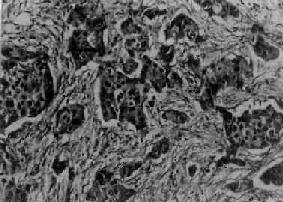

肉眼观,肿块一般较小,直径多为2~3cm,质硬,边缘不整,常可见到灰白色癌组织呈放射状侵入邻接纤维脂肪组织内。如果癌瘤位置浅,则可侵犯皮肤,与皮肤粘连并导致皮肤出现不规则浅表微小凹陷,呈橘皮样外观;如累及乳头,可出现乳头回缩、下陷现象(图13-25)。镜检,组织形态多样,癌细胞组成实体团块或腺样结构,两者常混合存在。其中多数病例主要由实体癌细胞团组成,称为实体癌。一般根据实体癌的癌实质与纤维组织间质比例的不同,又将其分为单纯癌(simple carcinoma),实质与间质量大致相等(图13-26);硬癌(scirrhous carcinoma),癌实质少而间质多;和不典型髓样癌(atypical medullary carcinoma),癌实质多而间质少,间质内常无淋巴细胞浸润(图13-27),癌细胞常呈多形性,核异型性明显,核分裂像易见。

癌细胞和间质量大致相等